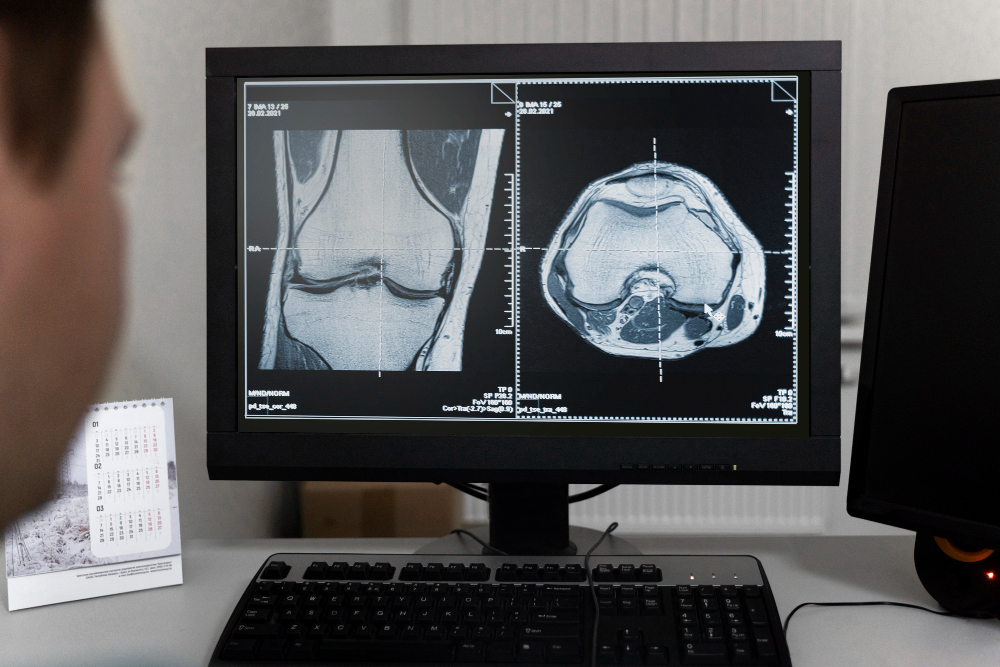

Unlock precise insights with our advanced radiology tests. From digital X-rays to ultrasound imaging, we ensure clarity and care. Trusted technology and expert radiologists for every diagnostic need.

- Our digital X-rays produce high-definition images, helping doctors detect even the smallest abnormalities with exceptional clarity and precision.

- All X-rays are reviewed by experienced radiologists, ensuring accurate analysis and trustworthy results you can rely on for treatment planning.

- Digital X-rays help diagnose fractures, infections, joint issues, and chest or abdominal problems with speed, accuracy, and clinical confidence.